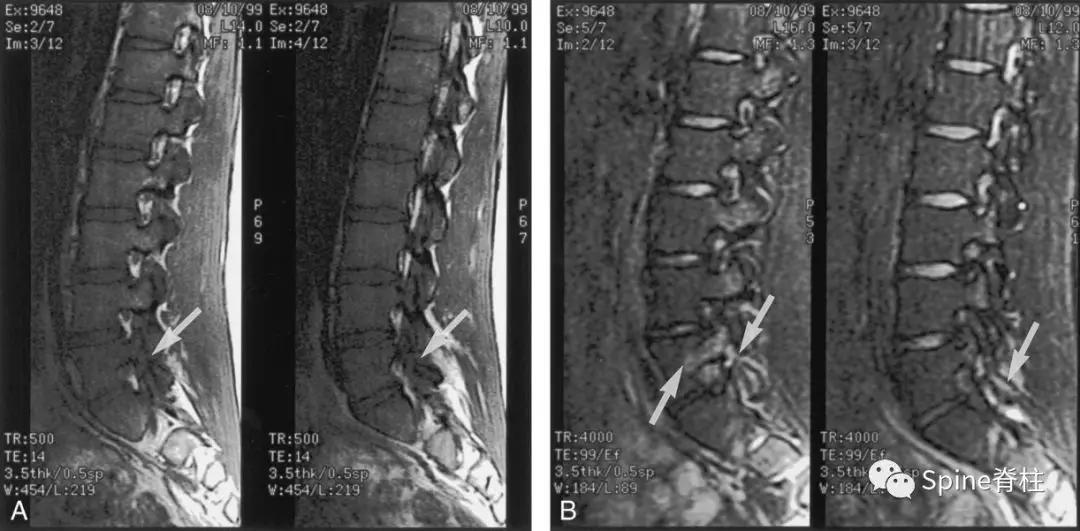

- 椎弓根出现T2高信号改变

Sairyo教授研究发现磁共振上 椎弓根出现T2高信号改变 (High signal changes) 是青少年和儿童峡部裂的早期诊断征象 。同时,存在椎弓根高信号改变也是保守治疗后能达到骨性愈合的良好预测指标(也就是说存在T2椎弓根右高信号改变的峡部裂患者,其峡部裂经保守治疗愈合的可能性大)。

图:右上图为椎弓根高信号改变(+),右下图为(-)

右图提示椎弓根高信号改变(箭头)

右图提示双侧椎弓根高信号改变(箭头)

右图:右侧椎弓根高信号改变明显,左侧椎弓根轻微高信号

因此, Sairyo教授也提出,对于青少年腰痛患者行MRI检查时,在传统椎间盘层面的基础上(A-C线), 多加一个经椎弓根层面(D线) (影像科医生希望能看到) 。因为,A-C线椎间盘层面可很好看出青少年腰椎间盘突出和腰椎椎体后缘离断症,而D线经椎弓根层面可以早期诊断出腰椎峡部裂和腰椎椎弓根损伤。